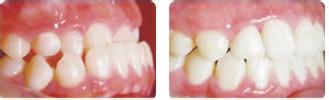

医学上对反颌的矫正原则是尽可能及早消除病因,早期矫治,可收到良好的矫治效果,并可防止畸形向严重发展。个别牙轻度的反颌可在医生的指导下,家长自行进行治疗。

多个牙反颌或畸形较严重时,则需要牙科医生用特殊的矫正器进行矫治。许多前牙反颌可单纯经过牙科医生进行矫治而恢复正常的咬颌功能和颜面的美观。

乳牙反颌轻度的可暂时不矫治,待乳牙脱落替换恒牙时,有的反颌畸形能自行矫正过来。而重度、显著的乳牙反颌,在4周岁时进行治疗为好。

替换牙期和恒牙早期,颌面部生长发育旺盛,反颌畸形如及时得到矫正,可收到事半功倍的效果,并能及时阻断颌骨的异常生长发育,是矫治反颌的关键时期。一般年龄在8-12岁。否则只好通过拔少牙齿矫治或正颌外科手术治疗,才能取得好的效果。>>>文字看累了?点击直接咨询医生吧!